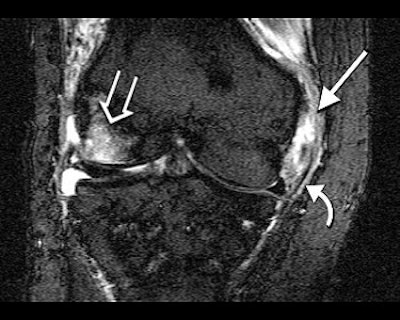

| Collateral ligament lesions (straight arrow), pericapsular edema (curved arrow) and edema-like bone marrow abnormalities (open arrow) were characteristic for the symptomatic side. Images courtesy of Dr. Marco Zanetti. |

The group concluded that type A tears are as common in the contralateral asymptomatic knee as in the symptomatic knee -- and that there is little evidence that such meniscal tears are responsible for pain. Instead, other types of meniscal tears, such as abnormalities of the collateral ligaments, pericapsular soft tissues, and bone marrow have a higher association with pain in the symptomatic knee.